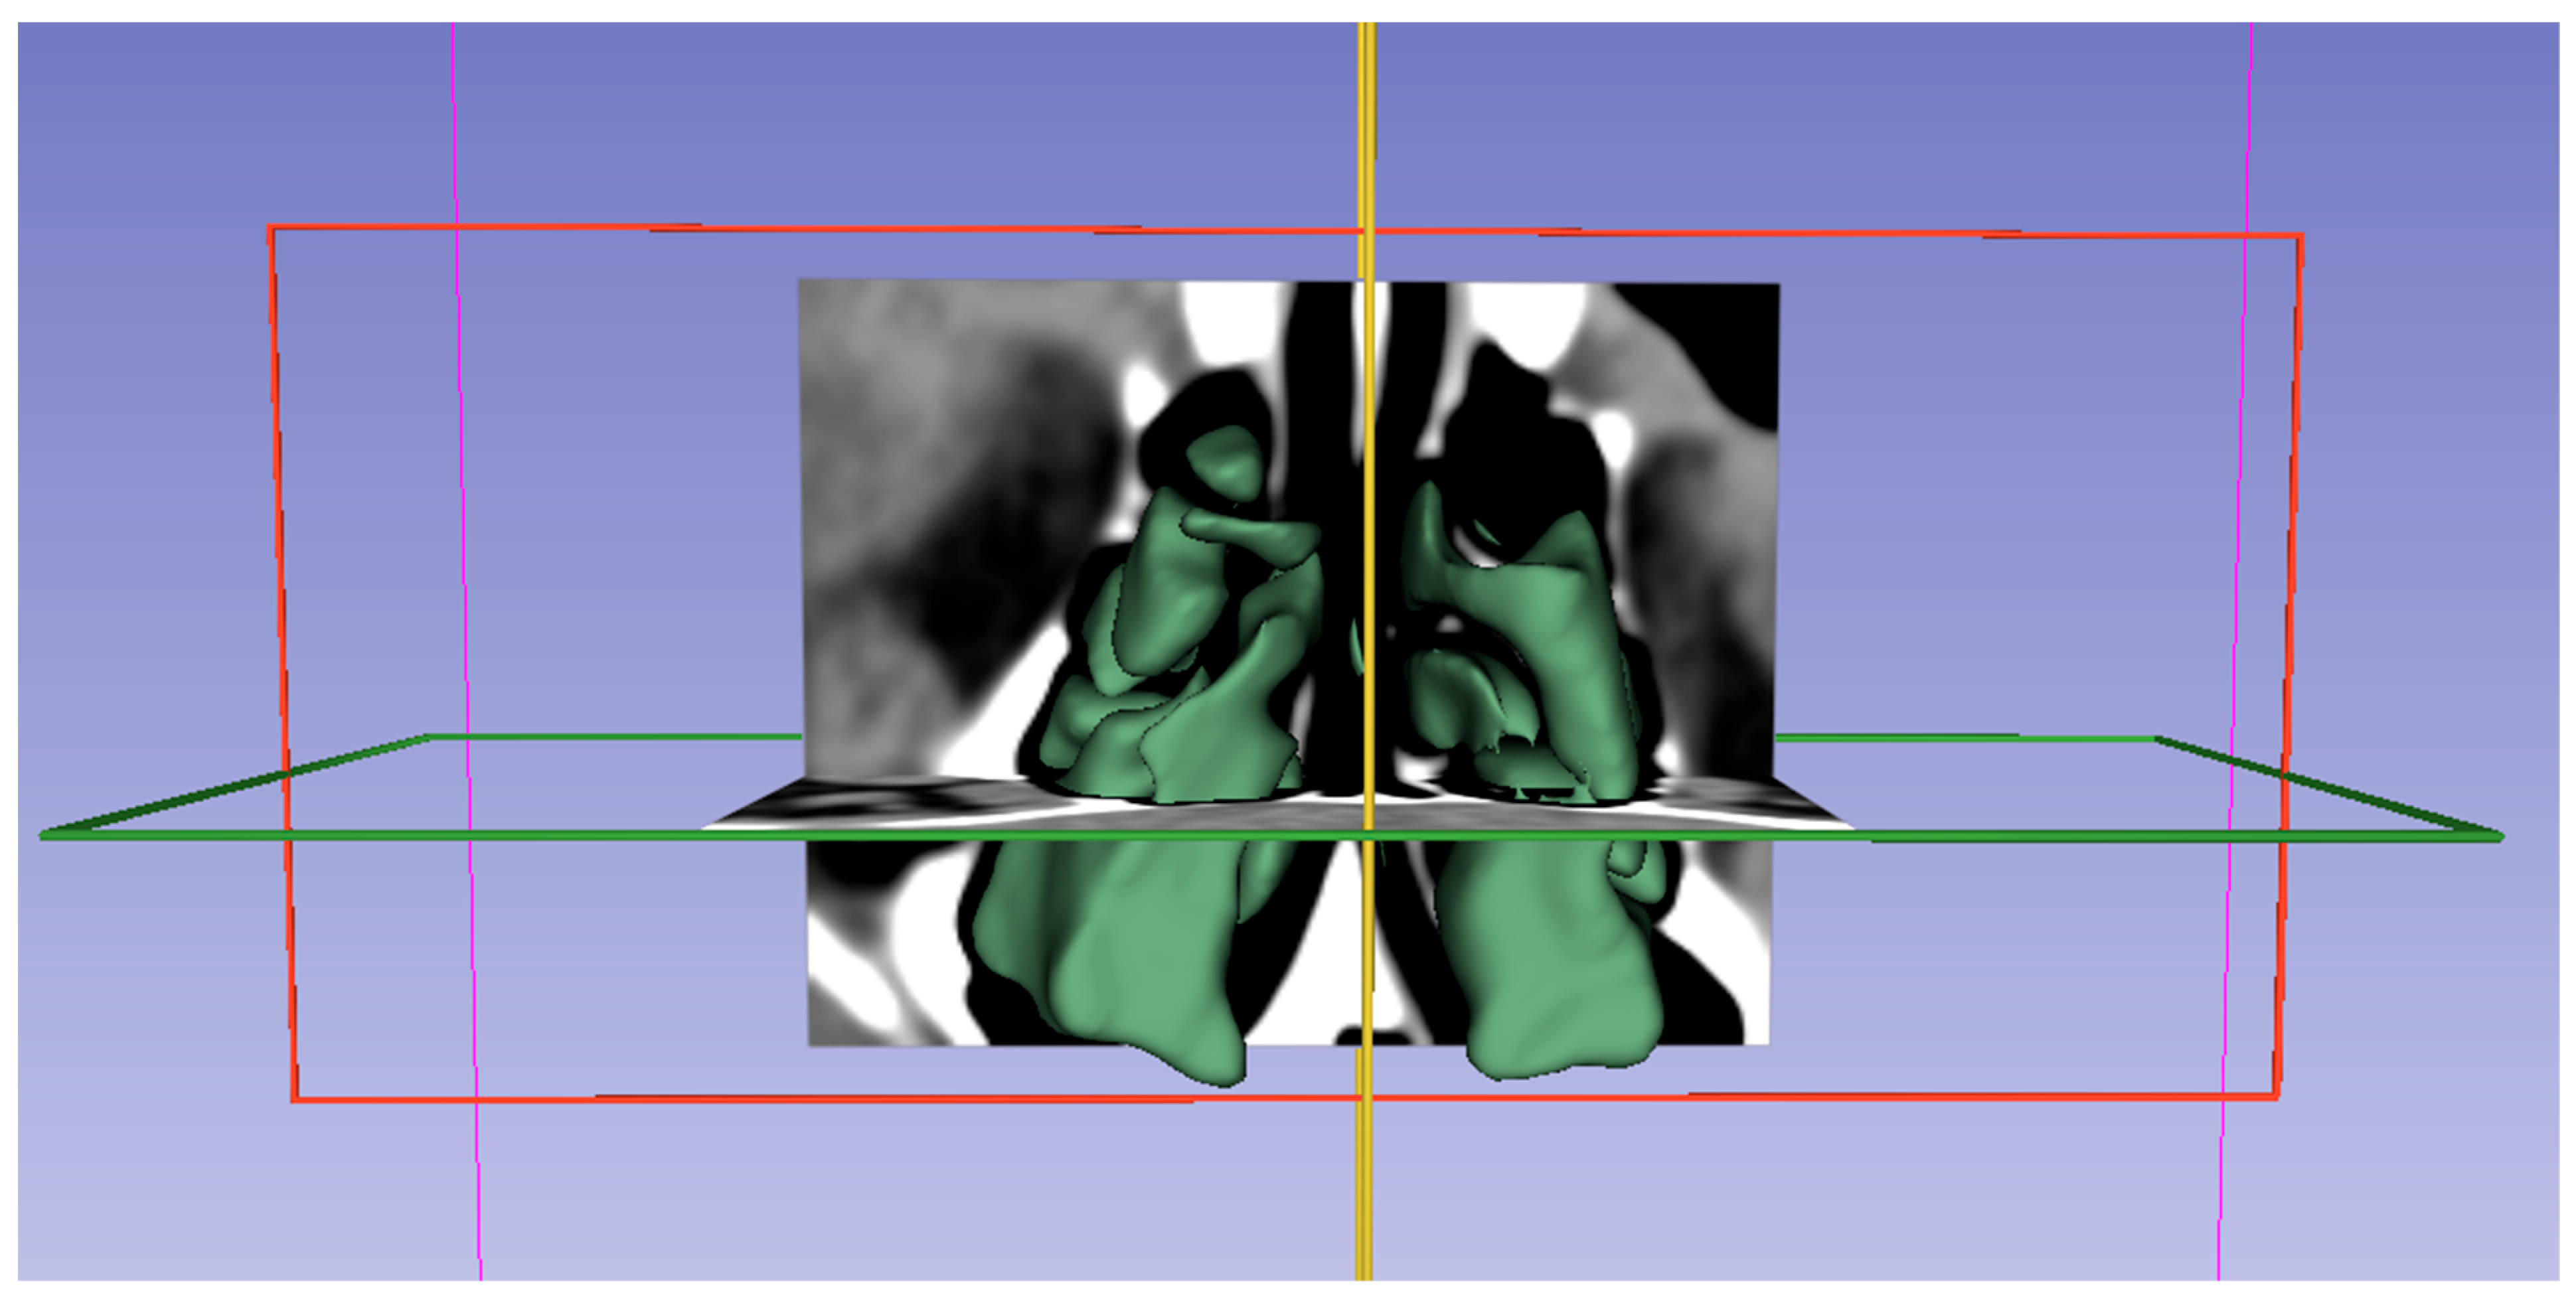

Figure 3. Images demonstrating the fully automated segmentation of the ethmoid sinus by the 3D Slicer application. Axial, coronal and sagittal views are shown in b, c and d, respectively.

We obtained subjects' CT images from our hospital's Picture Archiving and Communication System (PACS) and saved them in Digital Imaging and Communications Medicine (DICOM) format. DICOM data were then transferred to a personal computer. 3D Slicer (https://www.slicer.org/, version 5.3.1), a fully automated open-source software, was used for analysis (accessed on 5 Sep 2025) [9]. Images were displayed in the axial, coronal, and sagittal planes using the 3D Slicer application, and segmentation was performed (Figure 3 and Figure 4). The following steps were followed to select images suitable for segmentation and perform volumetric measurements.